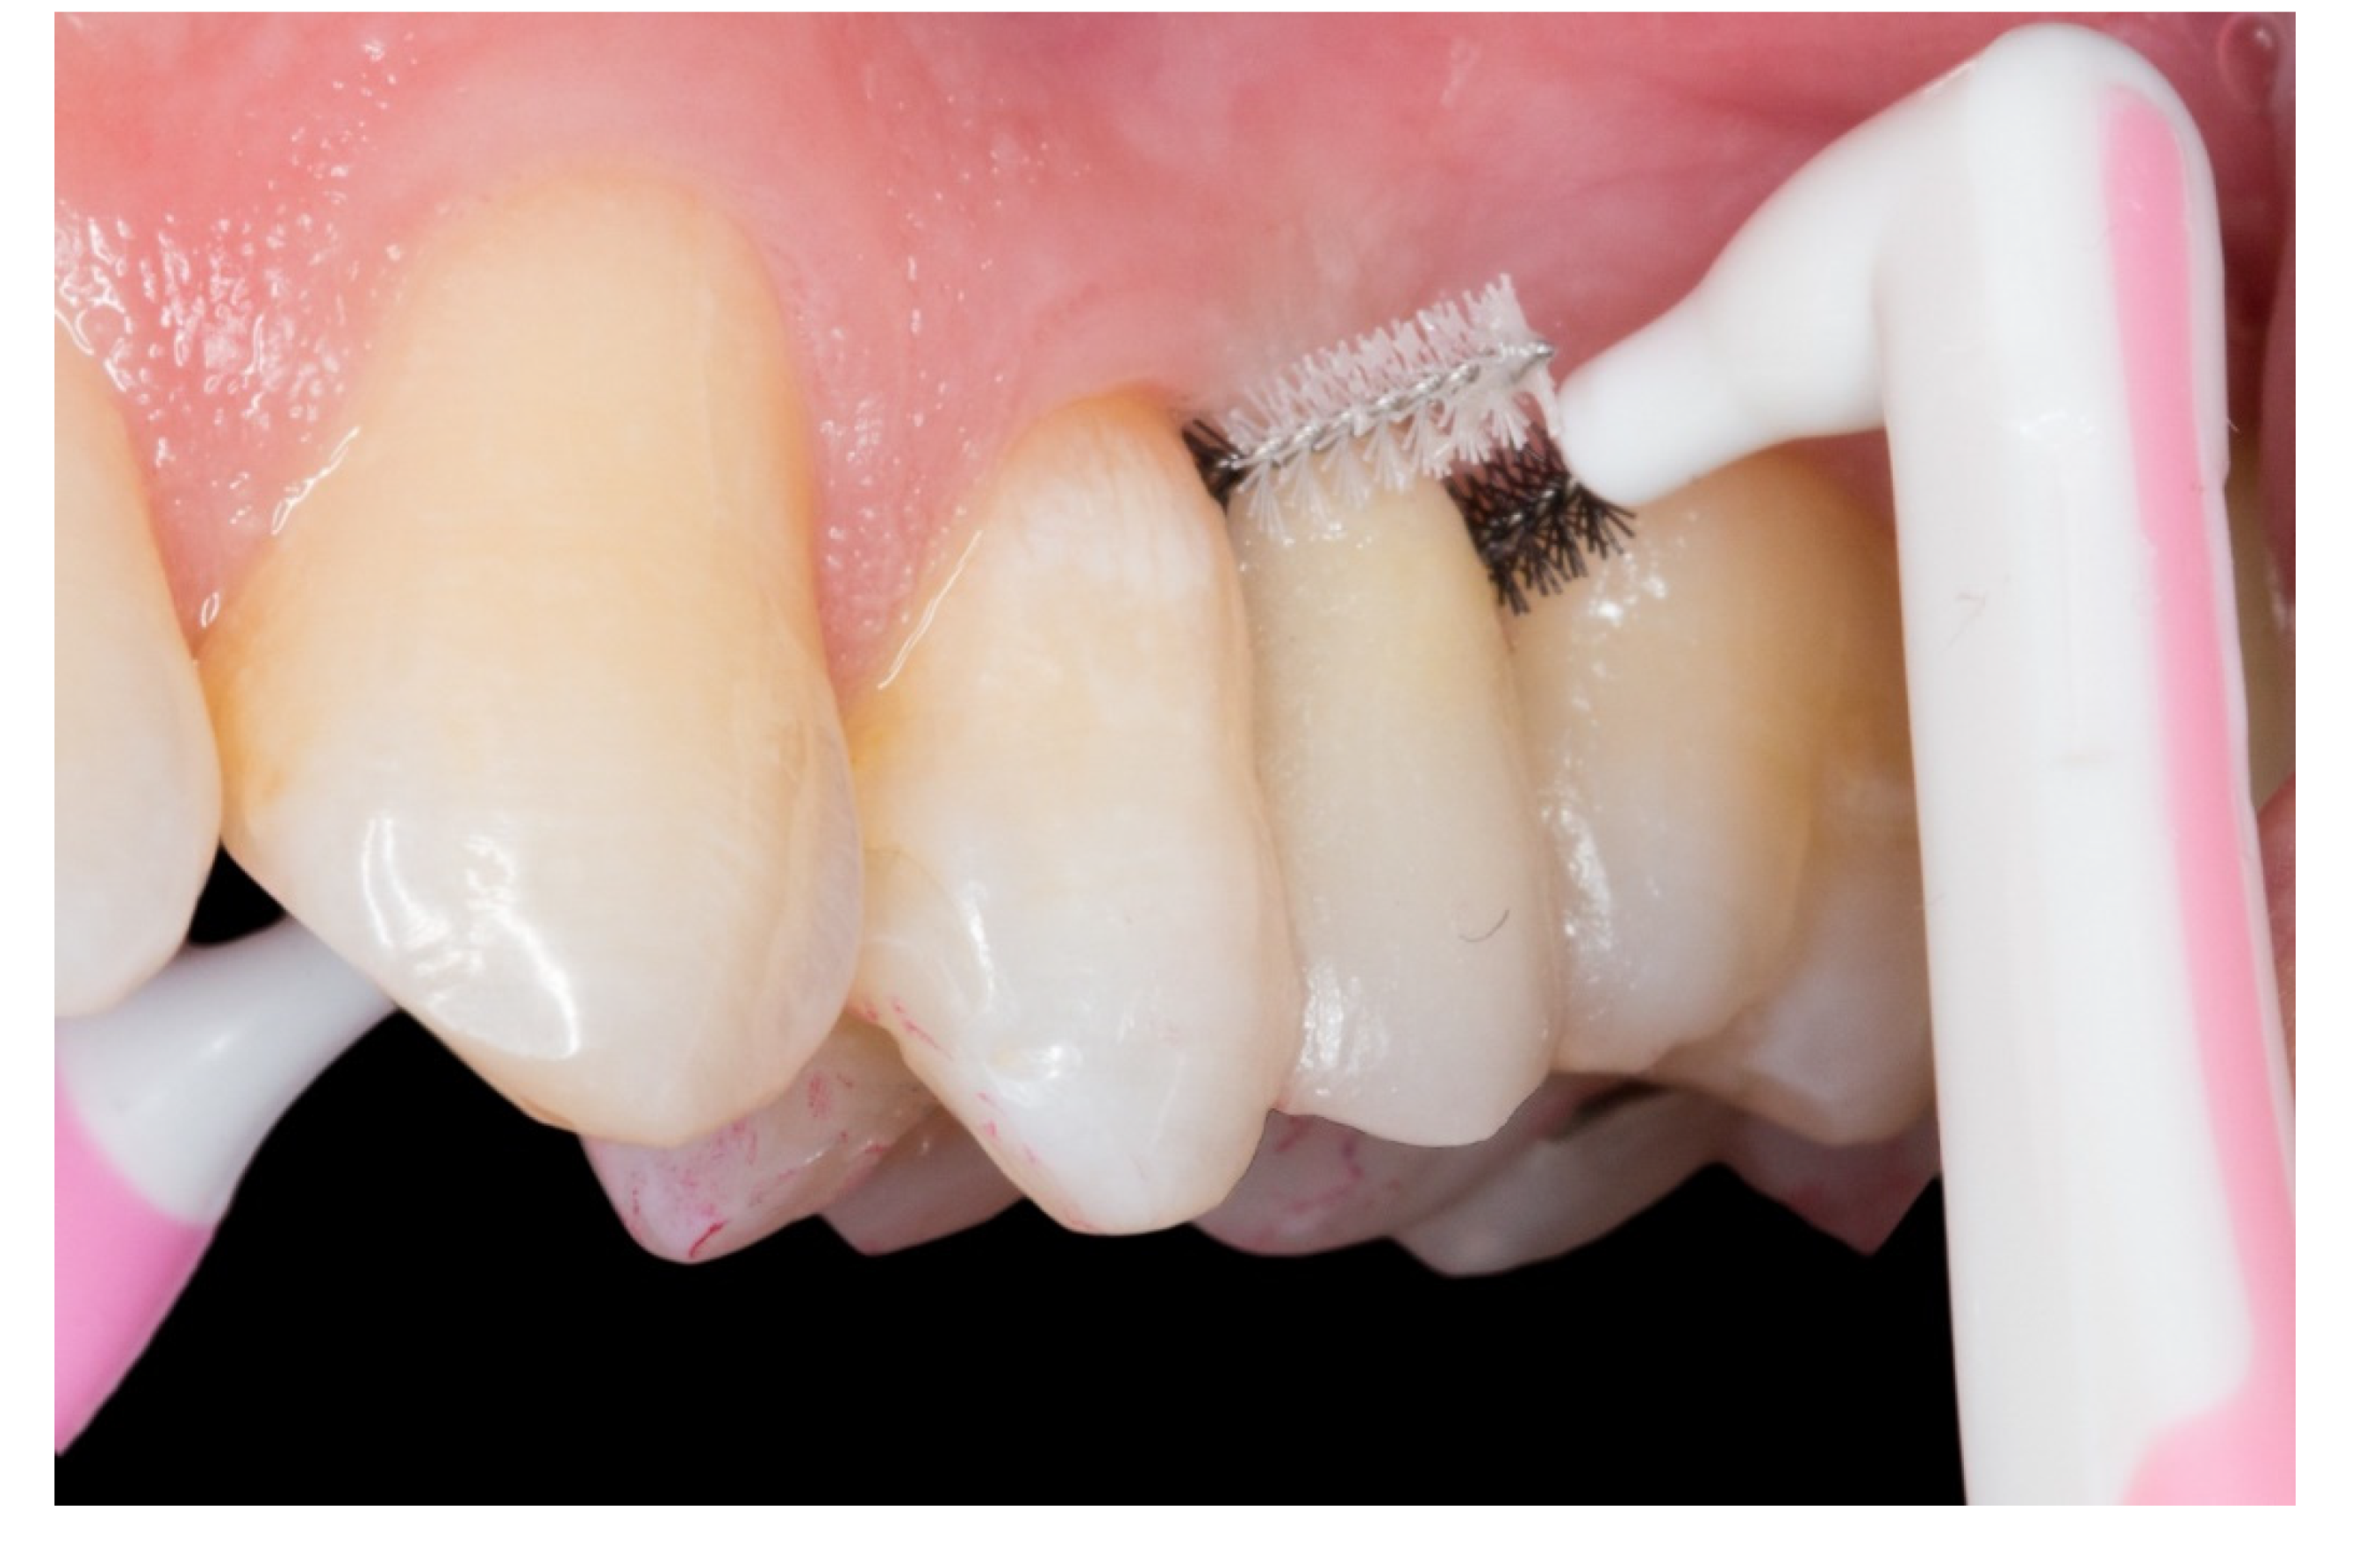

- The periodontal inflammation aspect on the pontic area: the framework design releases the embrasures allowing adequate interproximal brushing, avoiding periodontal disease and interproximal caries.